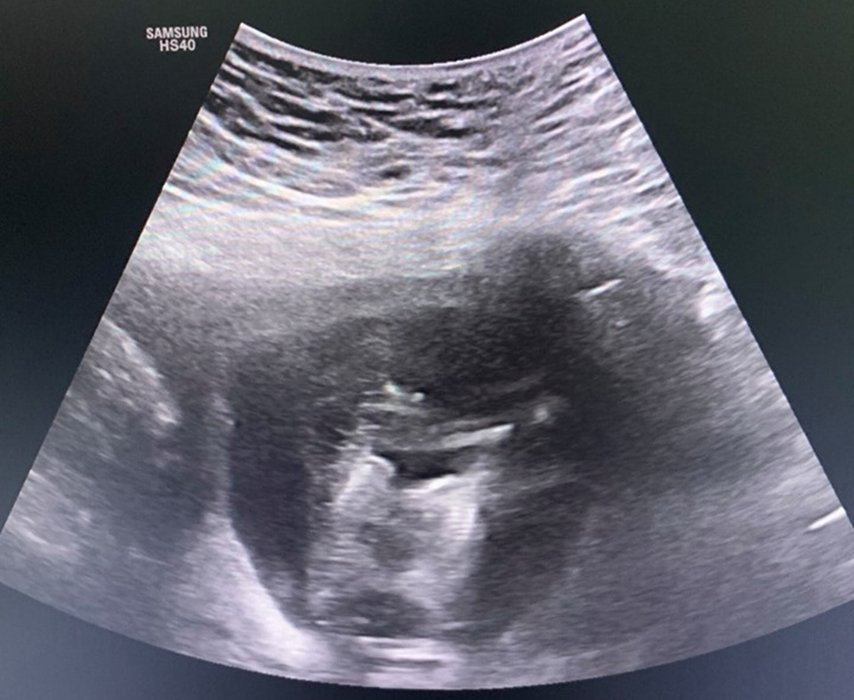

Hình ảnh ca song thai hiếm gặp. (Ảnh: BSCC)

Chị P. mang thai lần đầu, có thai tự nhiên. Kết quả khám cho thấy, chị đang mang song thai ở tuần thứ 12 và điều đặc biệt là 2 thai dính nhau từ phần phần ngực xuống đến phần bụng, có chung một quả tim. Cả 2 thai đều có tăng khoảng sáng sau gáy (2,5mm và 8,0mm).